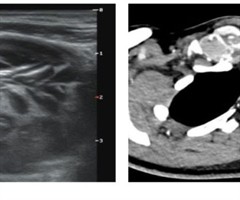

乳腺癌相关参数联合腋窝淋巴结超声阳性特征对淋巴结转移负荷的预测价值

[摘要]目的:分析乳腺癌相关参数及腋窝淋巴结阳性超声特征,探讨腋窝淋巴结转移负荷的危险因素,为乳腺癌患者术前评估提供依据。方法:回顾性分析经手术病理证实存在腋窝淋巴结转移的574例乳腺癌患者的超声和临床病理资料,根据腋窝淋巴结转移情况,分为...